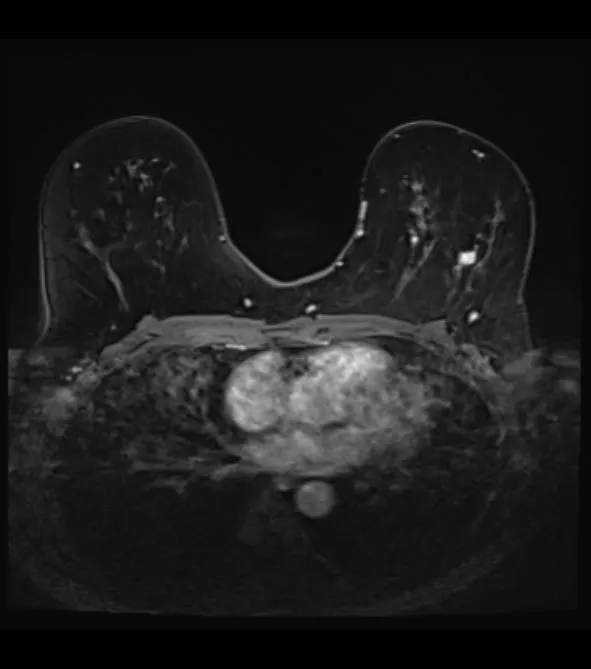

乳腺MRI検査は、痛みもなく、着衣のままで検査を受けることができます。死角もなく、マンモグラフィよりも正確な診断が可能と思われます。

そのため、当院では、人間ドック(保険外の自費診療)での乳腺MRI検査を行っております。病変をより正確に描出するために、造影剤を用いた乳腺MRI検査も行っております(なお、造影剤を用いる際には、腎機能の評価が必要ですので、3ヶ月以内の採血検査結果を持ってきていただくか、当院での迅速検査を受けて頂くことが必要になります)。